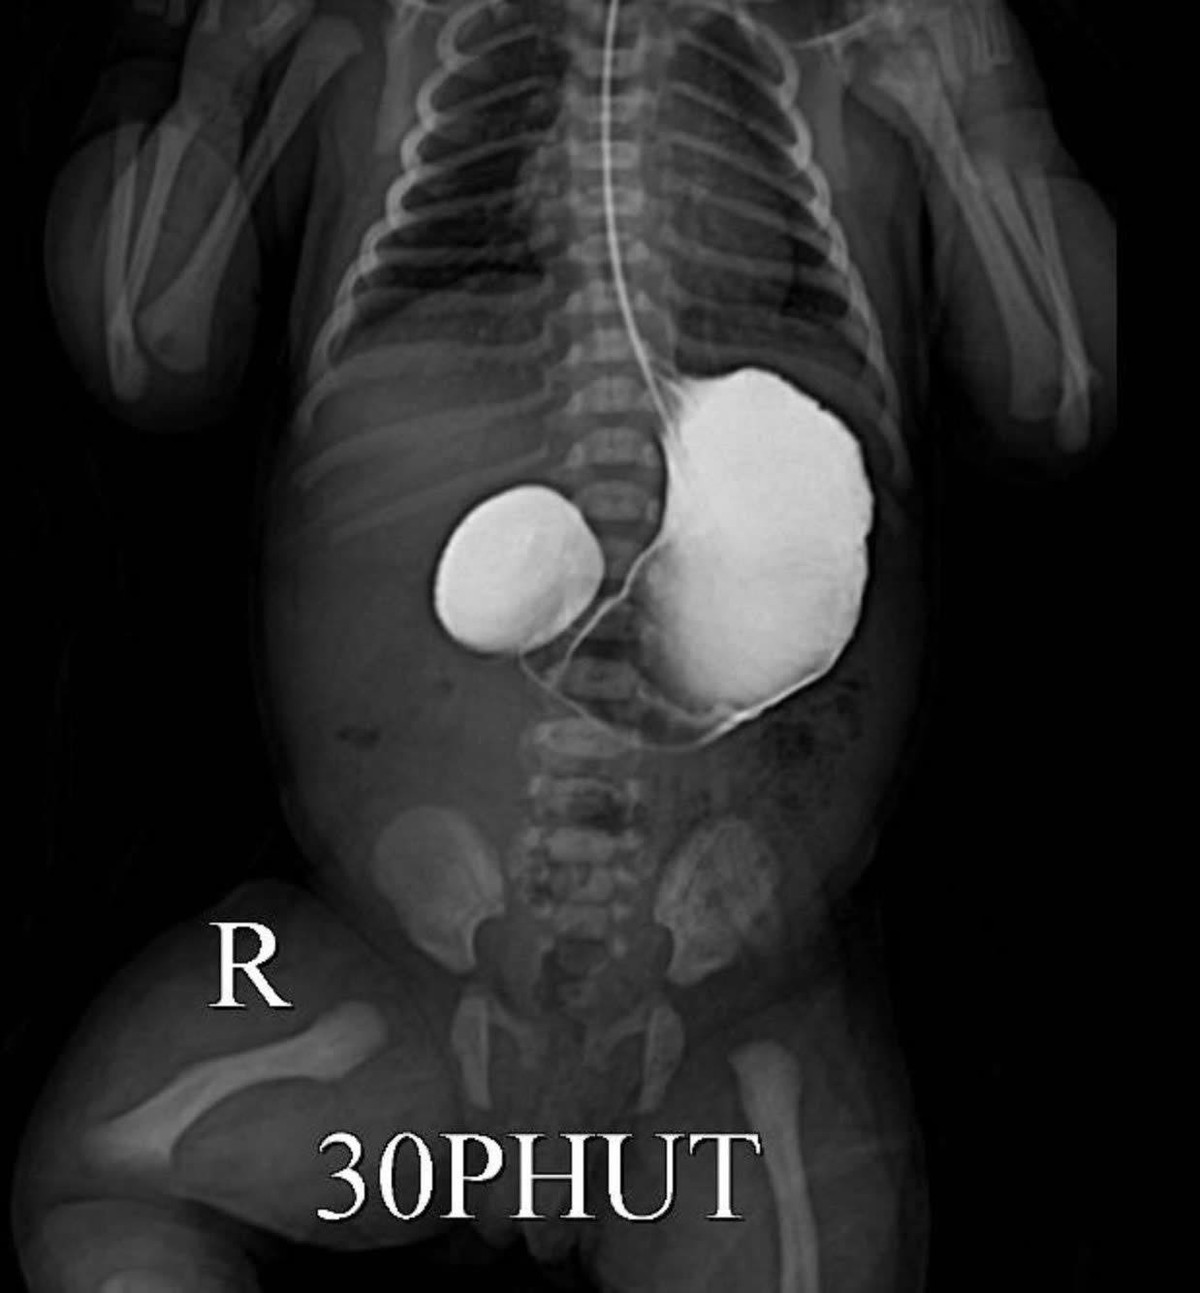

Hình ảnh bệnh lý trên phim chụp - Ảnh BVCC

Sau sinh, bé gái nặng 2,1 kg, tỉnh nhưng xuất hiện các triệu chứng: Nôn nhiều, mất nước, rối loạn điện giải. Qua kiểm tra và chụp x-quang, các bác sĩ chẩn đoán: Tắc tá tràng nguy cơ sốc giảm thể tích; Suy dinh dưỡng bào thai.